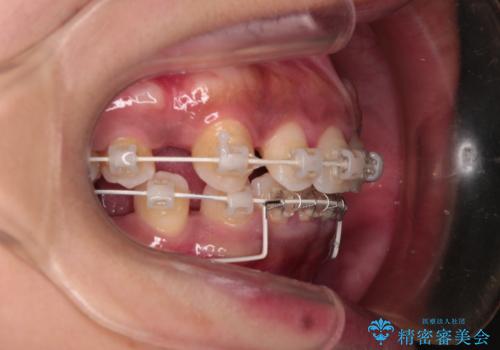

- 矯正装置

- 審美装置

「矯正装置が目立つのは避けたい」というご希望があったため、プラスチックブラケット+コーティングワイヤーを使用した審美装置を選択しました。